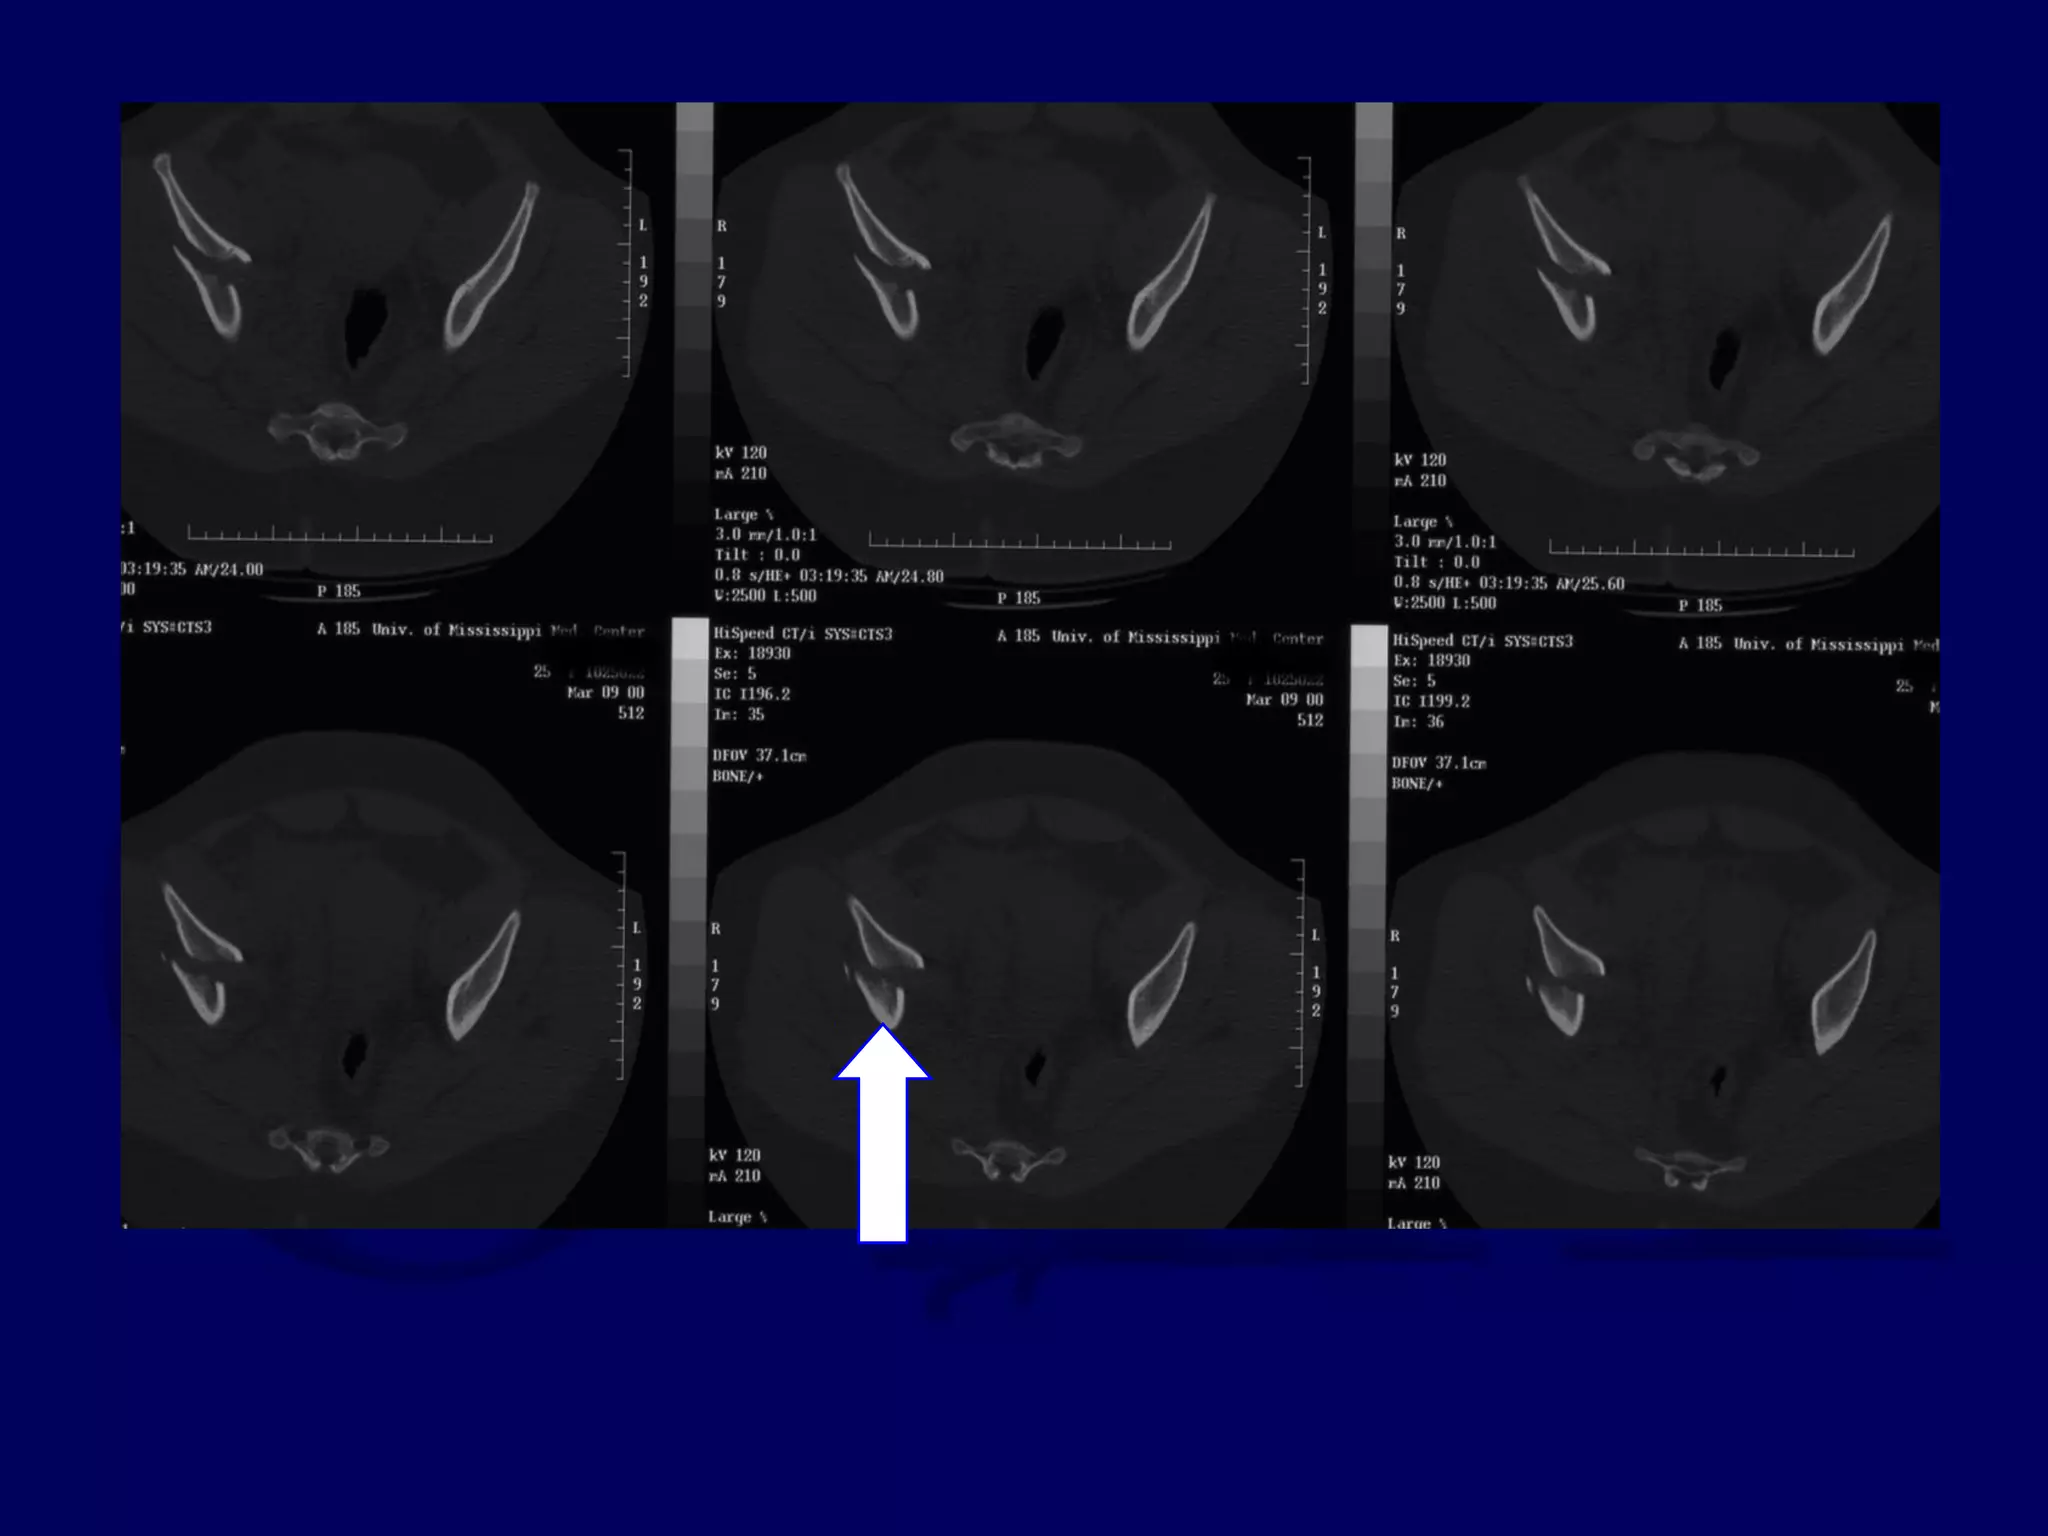

Posterior Wall Fx

63 Y.O. Male

L.W. 00.09.23